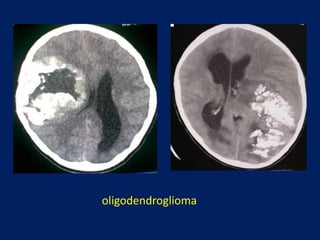

oligodendroglioma